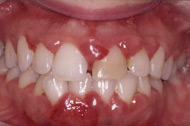

1. 刷牙或咬硬物時(shí)牙齦出血。正常的牙齦是不應(yīng)當(dāng)出血的。牙齦出血是牙周炎最早期的癥狀之一,是機(jī)體發(fā)出的信號(hào),告訴你牙齦發(fā)炎了,如果你不重視這個(gè)信號(hào),那么牙周炎就會(huì)繼續(xù)發(fā)展下去。

??????????????????

?